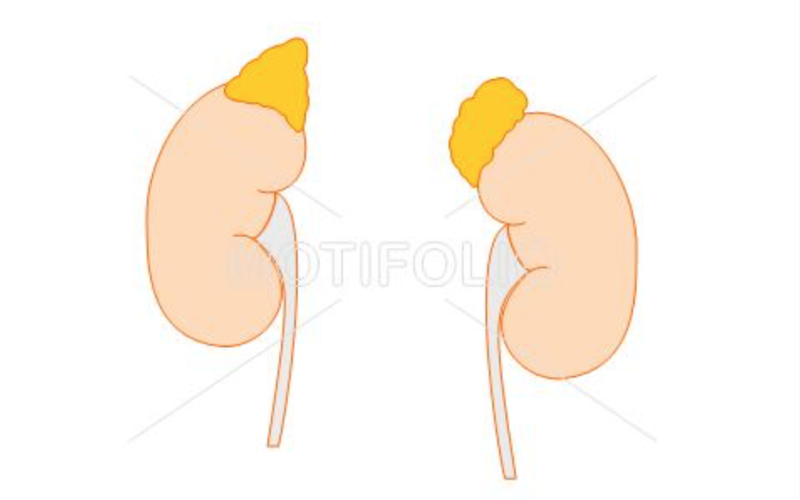

Adrenal Gland